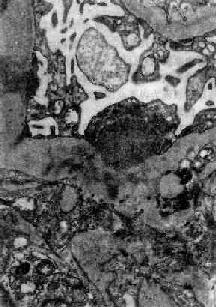

图12-8 毛细血管内增生性肾小球肾炎 电镜下见肾小球毛细血管基底膜表面上皮细胞下有多数驼峰状电子致密沉积物

图12-9 毛细血管内增生性肾小球肾炎 电镜下见驼峰状沉积物位于毛细血管基底膜表面。沉积物表面有上皮细胞覆盖,上皮细胞足突消失 免疫荧光法检查显示,在肾小球毛细血管壁表面有免疫球蛋白和补体沉积(主要为IgG和C3),呈颗粒状荧光。系膜内也可有类似沉积物。 肾小球的病变可引起相应的肾小管缺血,肾小管上皮细胞常有浊肿、玻璃样变和脂肪变等。管腔内含有从肾小球滤过的蛋白、红细胞、白细胞和脱落上皮细胞。这些物质在肾小管内凝集,形成各种管型,如蛋白管型、透明管型、细胞管型(如红细胞、白细胞或上皮细胞管型)、颗粒管型。 肾间质内常有不同程度的充血、水肿和少量淋巴细胞、中性粒细胞浸润。 肉眼观,早期变化不明显。以后肾轻度或中度肿大、充血、包膜紧张、表面光滑、色较红,故称大红肾。若肾小球毛细血管破裂出血,肾表面及切面可见散在的小出血点如蚤咬状,称蚤咬肾。切面可见皮质由于炎性水肿而增宽,条纹模糊与髓质分界明显。 【临床病理联系】 这种肾炎的主要临床症状为尿的变化,水肿和高血压。 1.尿的变化由于肾小球毛细血管损伤,通透性增加,故常有血尿、蛋白尿、管型尿等。 (1)血尿:血尿常可反映肾小球毛细血管损伤的情况。轻度血尿需用显微镜才能发现。严重的血尿,肉眼可见尿呈鲜红色。有时尿中红细胞溶解,血红蛋白在酸性尿中转变成酸性血红素,使尿呈棕红色。 (2)蛋白尿:蛋白尿的程度不同,一般不很严重,但少数病人尿中可有大量蛋白质。 (3)管型尿:在肾小管内凝集形成的管型随尿液排出,尿液内可出现各种管型,称为管型尿。 (4)少尿:由于肾小球细胞增生肿胀,压迫毛细血管,致管腔狭小,肾血流受阻,肾小球滤过率降低,而肾小管再吸收无明显障碍,可引起少尿,致水钠在体内潴留。严重者并可有含氮代谢产物潴留,引起氮质血症。 2.水肿病人常有轻度或中度水肿,往往首先出现在级织疏松的部位如眼睑。水肿的原因主要是由于肾小球滤过减少,而肾小管再吸收功能相对正常,引起水钠潴留。此外,也可能与变态反应所引起的全身毛细血管痉挛和通透性增加有关。 3.高血压病人常有轻至中度高血压。过去认为这种肾炎时的高血压与肾小球毛细血管阻塞,肾组织缺血引起肾素分泌增加有关。但病人血中肾素浓度多在正常范围之内。因此高血压的主要原因可能与水钠潴留引起的血量增加有关。严重的高血压可导致心力衰竭及高血压性脑病。 【结局】 这种肾炎的预后与年龄和病因有一定关系。儿童链球菌感染后肾小球肾炎的预后很好,95%以上可在数周或数月内症状消失,病变消退,完全恢复。少数病人病变消退较慢,肾小球系膜增生,可持续数月甚至1~2年。临床上,病人常有迁延性蛋白尿和复发性血尿。有时无明显症状,成为隐匿性肾炎。这种病变大多以后仍可消退,恢复正常。少数病人(约占1%~2%)临床症状消失,但病变持续不退,以后症状可反复,逐渐发展为慢性硬化性肾小球肾炎。极少数病人病变严重,发展较快,同时有明显的肾球囊上皮细胞增生,形成大量新月体,可发展为新月体性肾小球肾炎。这些病人常迅速发生急性肾功能衰竭,预后差。还有极少数(<1%)病人病变严重,发展迅速,在短期内发生肾功能衰竭、心力衰竭或高血压性脑病。 一般成人患感染后肾小球肾炎者预后较差,发生肾功能衰竭和转变为慢性肾炎者较多。此外,由其他感染引起的肾炎转变为慢性肾小球肾炎者,比链球菌感染后肾炎转为慢性者多见,预后也较差。